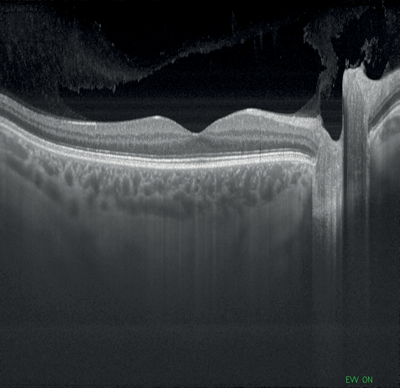

Figures 1-4: Swept-source OCT (DRI OCT-1 Triton, Topcon) images of healthy eyes that clearly delineate features in the vitreous, including area of Martegiani, bursa premacularis and posterior hyaloid, right through to the sclera, in the same single scan.

Figure 5: Colour fundus photograph of healthy eye taken

using swept-source OCT (DRI OCT-1 Triton, Topcon).